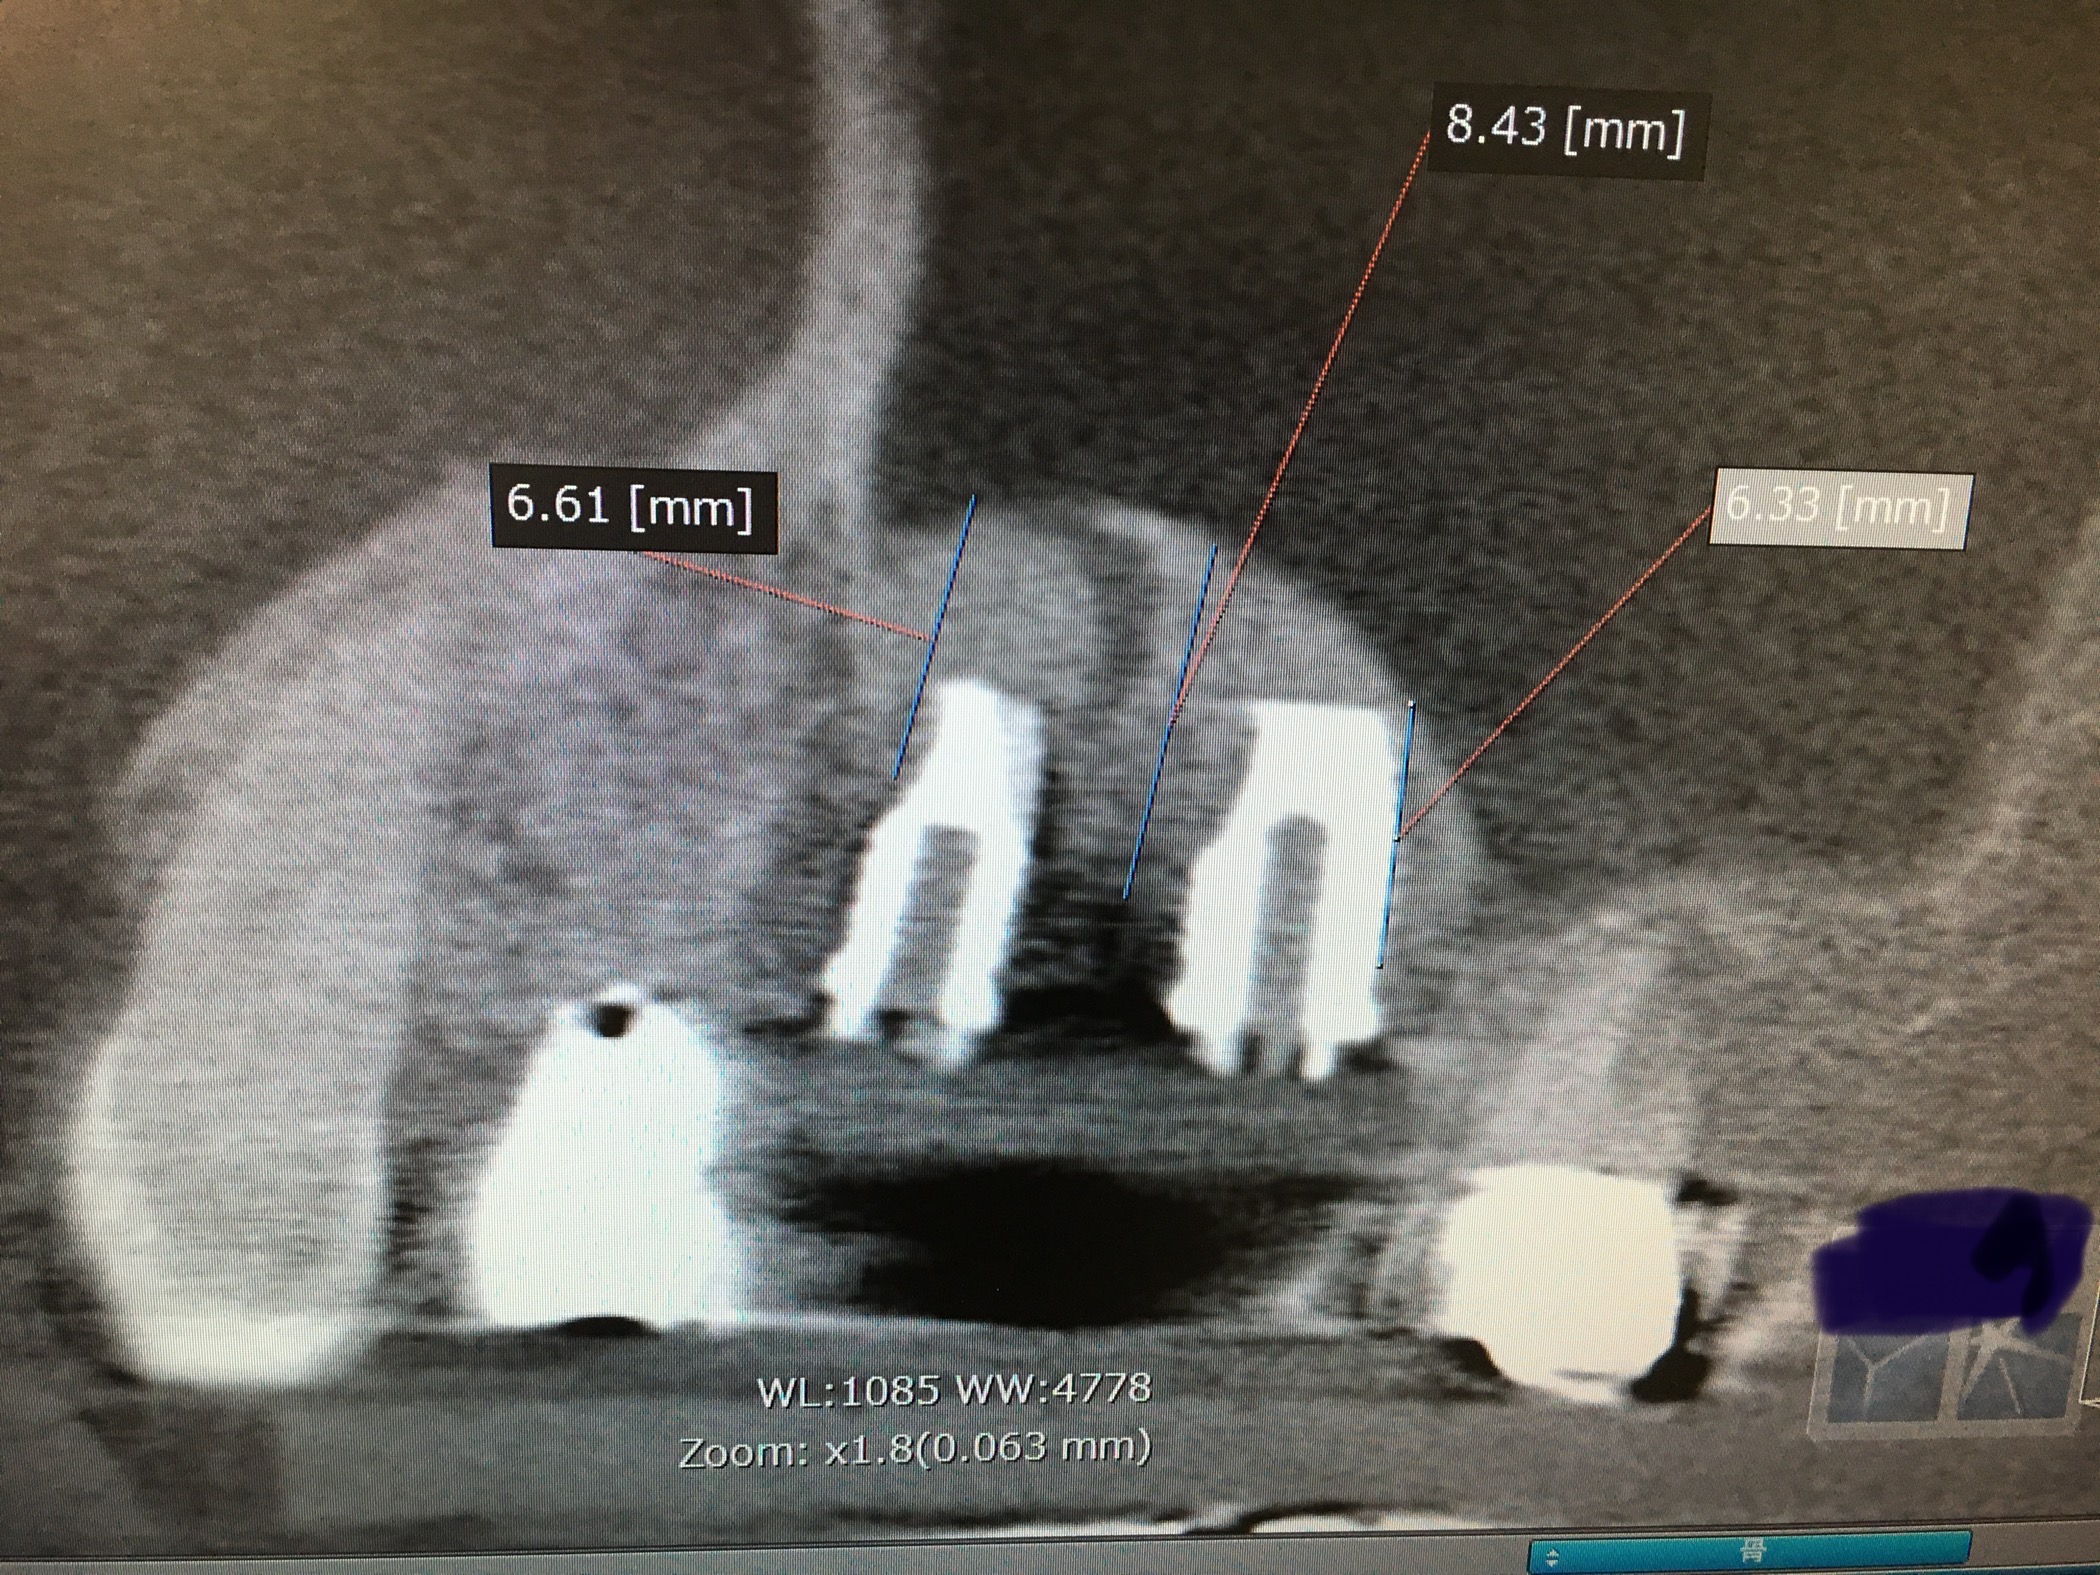

4年前に右上5.6のソケットリフトされた方です

現在の手法とは違い、人工骨β-Tcpを多方面から、めい一杯填塞した時の画像

4年後の本日の画像

填塞した人工骨は吸収され、本体フィクスチャーの周りは紙一枚の自家骨が巻き付いている状態です

今は、粘膜肥厚はありませんが、時に耳鼻科医が上積みの骨が無い為に、突出と誤りがちなケースです

今見て顧みると、侵襲が大きいなあ、現在はデンサーを使い自家骨だけでの挙上が可能ですね!